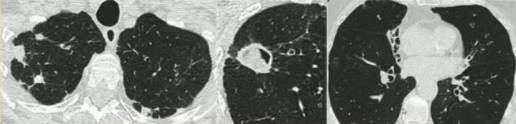

单纯肺曲菌球:非免疫受损病人,有较少或没有症状,含真菌球单发空洞,具有曲霉菌血清学和微生物学依据(阳性结果),至少观察3个月没有放射影像学的进展。

慢性空洞性肺曲霉病(CCPA):最常见,单发或多发的肺空洞(薄壁或厚壁),空洞内可包含一个或多个曲菌球或不规则的腔内物质,具有曲霉菌血清学和微生物学依据,并有明显肺部和全身症状,至少3个多月的观察有放射影像学进展(新发空洞,空洞外周浸润增加及纤维增生增加)。

曲霉结节:不常见,单发或多个结节(<3cm),有或没有空洞,常出现坏死,但不表现为组织侵袭。易与结核、肺癌、肺球孢子菌及其他疾病混淆,只能依靠组织学明确诊断。

亚急性侵袭性肺曲霉病(SAIA):轻度免疫缺陷的侵袭性肺曲霉病患者,发生在1-3个月内,具有可变的影像学特征,包括空洞、结节、有“脓肿形成的进展性实变”。最重要的特征为肺组织发现菌丝,另血液或呼吸液GM试验呈强阳性。